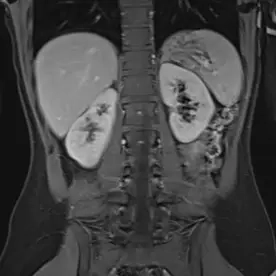

Es erfolgte eine MRT der Nieren mit intravenöser Kontrastmittelgabe und urographischer Phase zur dedizierten Darstellung der ableitenden Harnwege. Es bestätigte sich eine Anlagevariante der rechten ableitenden Harnwege, eine Doppelung des rechten proximalen Ureters mit Fusion im proximalen Drittel (Ureter fissus) bei regelrechter Darstellung der Nierenbeckenkelchsysteme (Bild 1). Im Nierenparenchym beidseits zeigen sich mehrere, keilförmige Areale mit Diffusionsstörungen und teils T2-hyperintensen Foci (Bild 2 und 3). Nach i.v. Kontrastmittelgabe zeigt sich ein weitesgehend unauffällig und homogen kontrastiertes Nierenparenchym beidseits (Bild 4).

Bild einer chronischen Pyelonephritis i.R. einer rezidivierender Reflux auf dem Boden eines Ureter fissus.